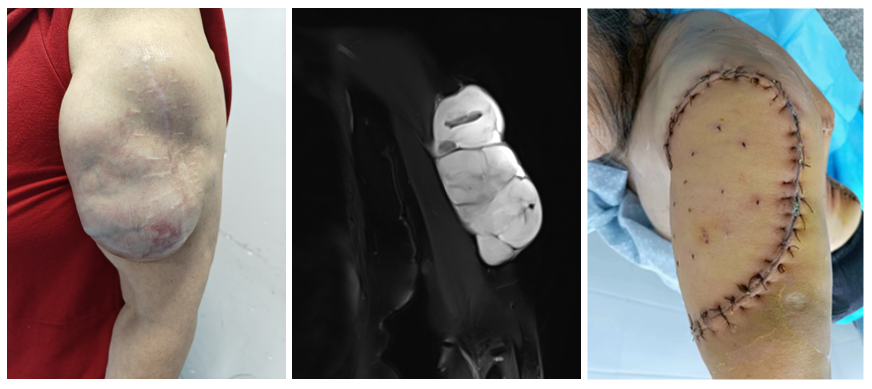

案例二 左肩胛区粘液纤维肉瘤(术后复发),转诊我院,在肩胛带全切除后进行屈肘功能重建手术。